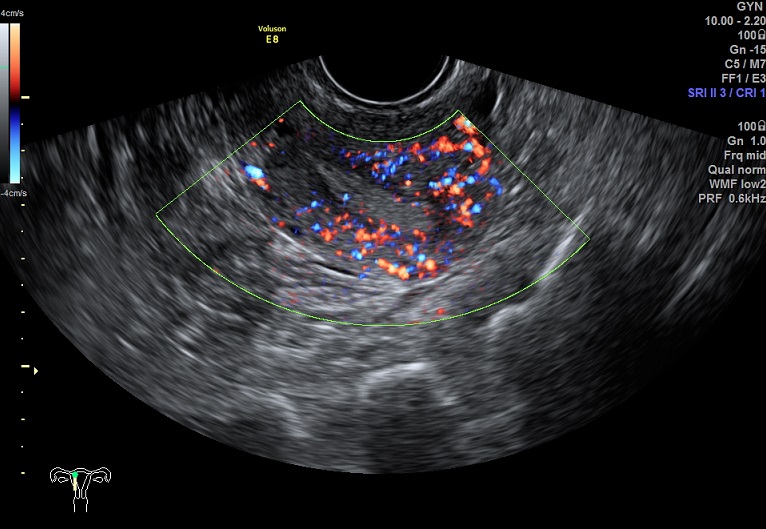

女性,25岁,原发性不孕2年。

2015-1-28 月经第18天检查

内膜血流:2级

容积:4.0ml